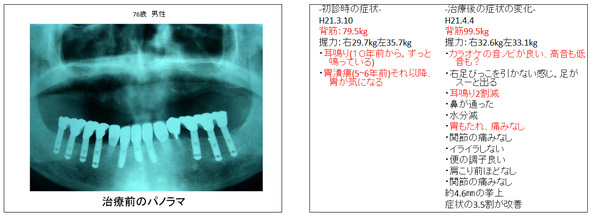

↑インプラント埋入により、義歯からまぬがれ固定することが出来た症例です。